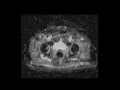

Bladder cancer with lymphadenopathy

MR images demonstrate a T1 hypointense, T2 hyperintense, avidly enhancing bladder mass with restricted diffusion and a metastatic lymph node along the right pelvic side wall.